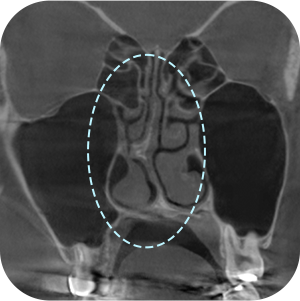

ตรจสอบผนังกั้นจมูก และโพรงจมูกภายใน

ตรจสอบตำแหน่งที่แน่นอน ของซิลิโคนเดิม

จำเป็นต้องถ่าย CT จมูกก่อนผ่าตัด ?

Aยิ่งเป็นกรณีผ่าตัดแก้ไข ก็ต้องยิ่งวิเคราะห์ละเอียดขึ้น!

การวิเคราะห์อย่างละเอียด จำเป็นอย่างมากต่อ การผ่าตัดแก้ไขจมูก

วิเคราะห์ได้อย่างละอียด

จากการถ่าย 3D-CT! - 03